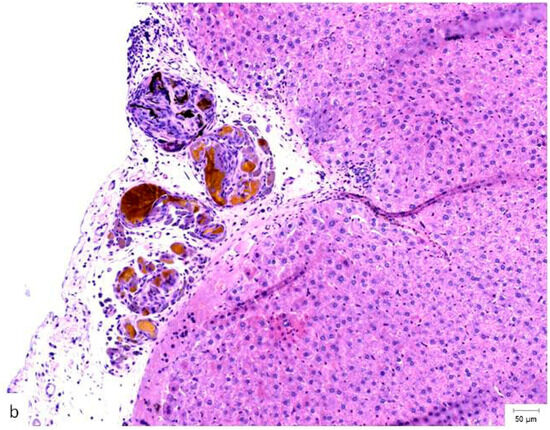

A comparison of the histopathological findings in the hepatic tissues of the three experimental groups on PO day 50 can be seen in Figure 4.

Figure 4.

Histopathological appearance of hepatic tissue from the three experimental groups at PO day 50; Hematoxylin and Eosin staining, ×10 magnification, the scale bar (right lower corner of each picture) is 50 µm. (a) Study group (CA + PLA patch): Section shows dense inflammatory infiltrate composed of both lymphocytes and scattered polymorphonucleated neutrophils concentrated around the adhesive interface and extending into the adjacent hepatic parenchyma. This mixed inflammatory reaction is indicative of an acute-on-chronic tissue response to the foreign material. Fibrosis was also detected, characterized by fibroblast proliferation and collagen deposition, consistent with early reparative remodeling. (b) Control group (electrocautery): Normal hepatic architecture is preserved, with no evidence of inflammatory infiltrate, necrosis, or fibrosis. The absence of immune cell recruitment indicates minimal tissue damage or foreign body reactions associated with electrocautery hemostasis. (c) Comparison group (TachoSil®): Mild, patchy lymphocytic infiltration was observed at the interface between the hepatic parenchyma and the remaining hemostatic material. The right portion of the image shows residual TachoSil matrix appearing as pale eosinophilic, acellular fragments, consistent with a fibrin-rich thrombin/fibrinogen composite undergoing resorption. No neutrophilic infiltration or fibrosis was evident.